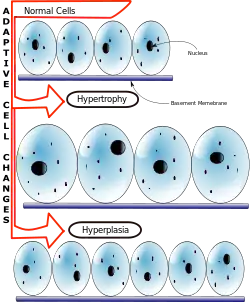

| Hypertrophy results from an increase in cell size, whereas hyperplasia stems from an increase in cell number. |

Hypertrophy is the increase in the volume of an organ or tissue due to the enlargement of its component cells.[1] It is distinguished from hyperplasia, in which the cells remain approximately the same size but increase in number.[2] Although hypertrophy and hyperplasia are two distinct processes, they frequently occur together, such as in the case of the hormonally induced proliferation and enlargement of the cells of the uterus during pregnancy.